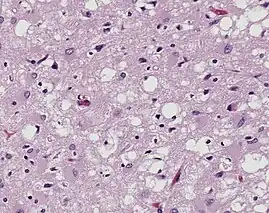

Prions are misfolded proteins that transmit their abnormal folding pattern to other copies of the protein without using nucleic acids. Besides obtaining prions from others, these misfolded proteins arise from genetic differences, either due to family history or sporadic mutations.[21] Plants uptake prions from contaminated soil and transport them into their stem and leaves, potentially transmitting the prions to herbivorous animals.[22] Additionally, wood, rocks, plastic, glass, cement, stainless steel, and aluminum have been shown binding, retaining, and releasing prions, showcasing that the proteins resist environmental degradation.[23]

Prions are best known for causing transmissible spongiform encephalopathy (TSE) diseases like Creutzfeldt–Jakob disease (CJD), variant Creutzfeldt–Jakob disease (vCJD), Gerstmann–Sträussler–Scheinker syndrome (GSS), fatal familial insomnia (FFI), and kuru in humans.[24]

While prions are typically viewed as pathogens that cause protein amyloid fibers to accumulate into neurodegenerative plaques, Susan Lindquist led research showing that yeast use prions to pass on evolutionarily beneficial traits.[25]